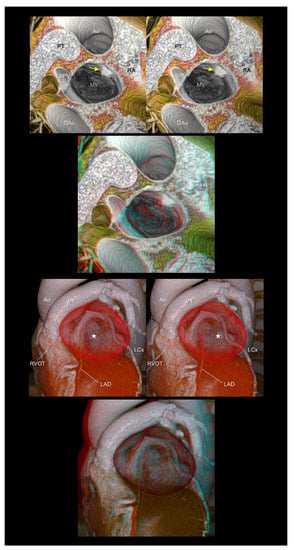

4.5. Valvar Heart Diseases

4.6. Congenital Heart Disease